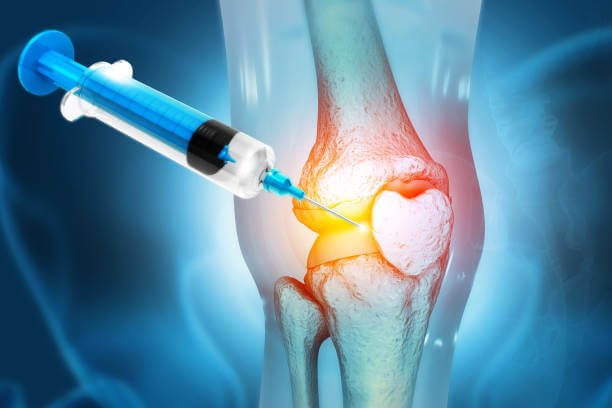

무릎 원인에 따라 약물치료, 주사치료, 수술적 치료를 시행합니다. 주사 치료의 경우 진통 및 소염 효과가 있는 스테로이드제와 연골을 보호하는 히알루론산 주사제를 사용하지만 이러한 치료로도 증상이 호전되지 않거나 초기 단계가 지난 경우에는 수술적 치료를 진행합니다.